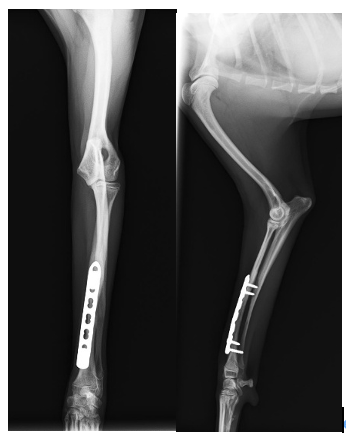

術後の経過は良好で、10日後には前足を負重し歩けるようになりました。

手術後2ヶ月で骨の癒合は完了しました。